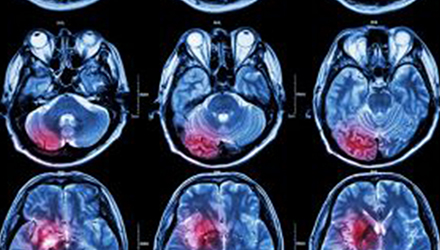

在這項(xiàng)研究中,研究人員使用功能核磁共振成像(fMRI)觀察大腦中血液含氧量的變化。研究人員首先研究了耳鳴患者和無(wú)耳鳴者的大腦活動(dòng),其目的是比較兩組受試者大腦處理情緒的方式。

在功能磁共振成像檢查中,受試者分別聽(tīng)30種“愉悅”的聲音、30種“不愉快”的聲音和30種“中性”的聲音。這些聲音包括小孩咯咯笑,嬰兒啼哭,以及熱水壺?zé)_(kāi)的聲音。

功能磁共振成像的結(jié)果顯示,當(dāng)暴露于情緒性聲音下,耳鳴患者大腦不同區(qū)域的活動(dòng)比沒(méi)有耳鳴者的活動(dòng)更強(qiáng)烈。接著,研究人員進(jìn)行了更深入的研究:耳鳴患者的大腦活躍性和耳鳴嚴(yán)重程度的關(guān)系。

調(diào)查結(jié)束后,再進(jìn)行功能核磁共振成像檢查。第二輪功能核磁共振成像顯示,那些耳鳴較輕的患者實(shí)際上使用了大腦不同的區(qū)域來(lái)處理情緒信息。

傳統(tǒng)觀點(diǎn)認(rèn)為,大腦中的扁桃體是處理情緒的關(guān)鍵,但此次研究發(fā)現(xiàn),那些不被耳鳴困擾的患者實(shí)際上使用更多大腦額葉來(lái)處理情緒。這類患者額葉活動(dòng)更顯著的原因是,額葉通常更多地用于注意力、計(jì)劃和沖動(dòng)的控制。